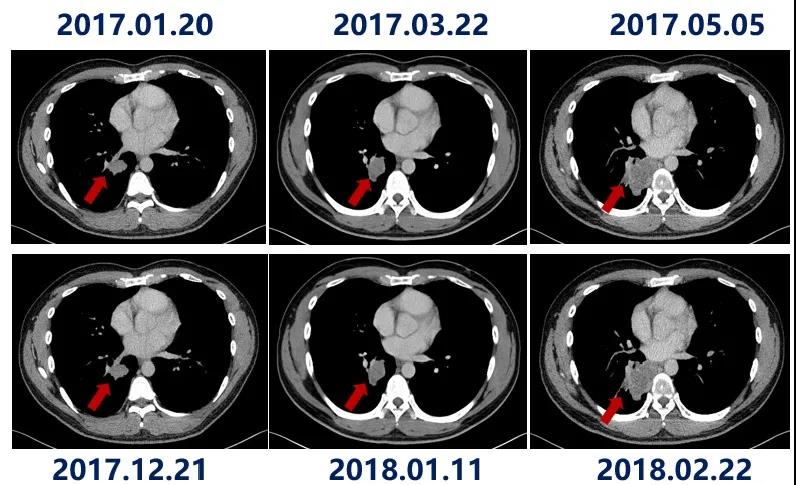

二线诊疗经过:一线索拉非尼治疗失败后,于2017-01-23至2018-02-01予卡瑞利珠单抗(3 mg/kg,每3周1次)治疗,PFS最终达13个月。主要不良事件为1级反应性皮肤毛细血管增生症和1级谷丙转氨酶升高。

最后,本例患者在治疗前两个月时病灶持续增大,而由第3个月起病灶开始缩小,最终达到PR。通常免疫治疗单独应用的起效时间为3个月左右,但有时临床医生也会遇到肿瘤假性进展的情况(总体发生率<10%)。虽然目前假性进展的发生机制尚无定论,但主流观点认为,大量T细胞和免疫调控细胞进入肿瘤病灶区域后,造成了影像学上肿瘤阴影面积的增大,但实际上这种增大并非来源于肿瘤细胞的复制,而是源于免疫细胞的聚集。因此,假性进展是免疫治疗中的一个利好现象。目前临床通常采用免疫治疗特有的评价标准,给予两次进展机会帮助辨别,除此以外临床医生还可以通过穿刺活检和监测ctDNA的方法协助判断。当然,最终是否继续用药还要结合患者的体能状况、全身症状和肿瘤标记物等情综合评估。